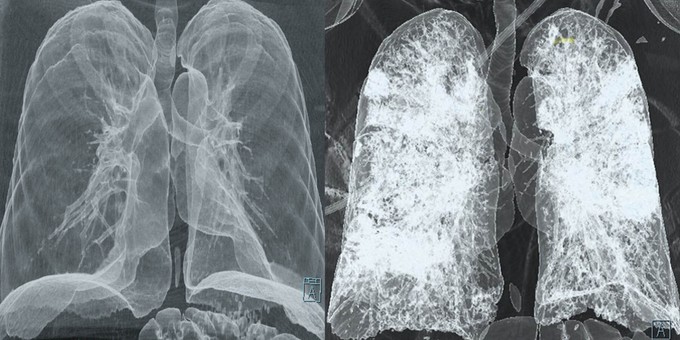

Ezekkel a vizsgálatokkal deríthető ki a szédüléses panaszok oka

Gyakorlatilag majdnem minden szédülést panaszoló páciensnél szükséges bizonyos vizsgálatokat elvégezni.